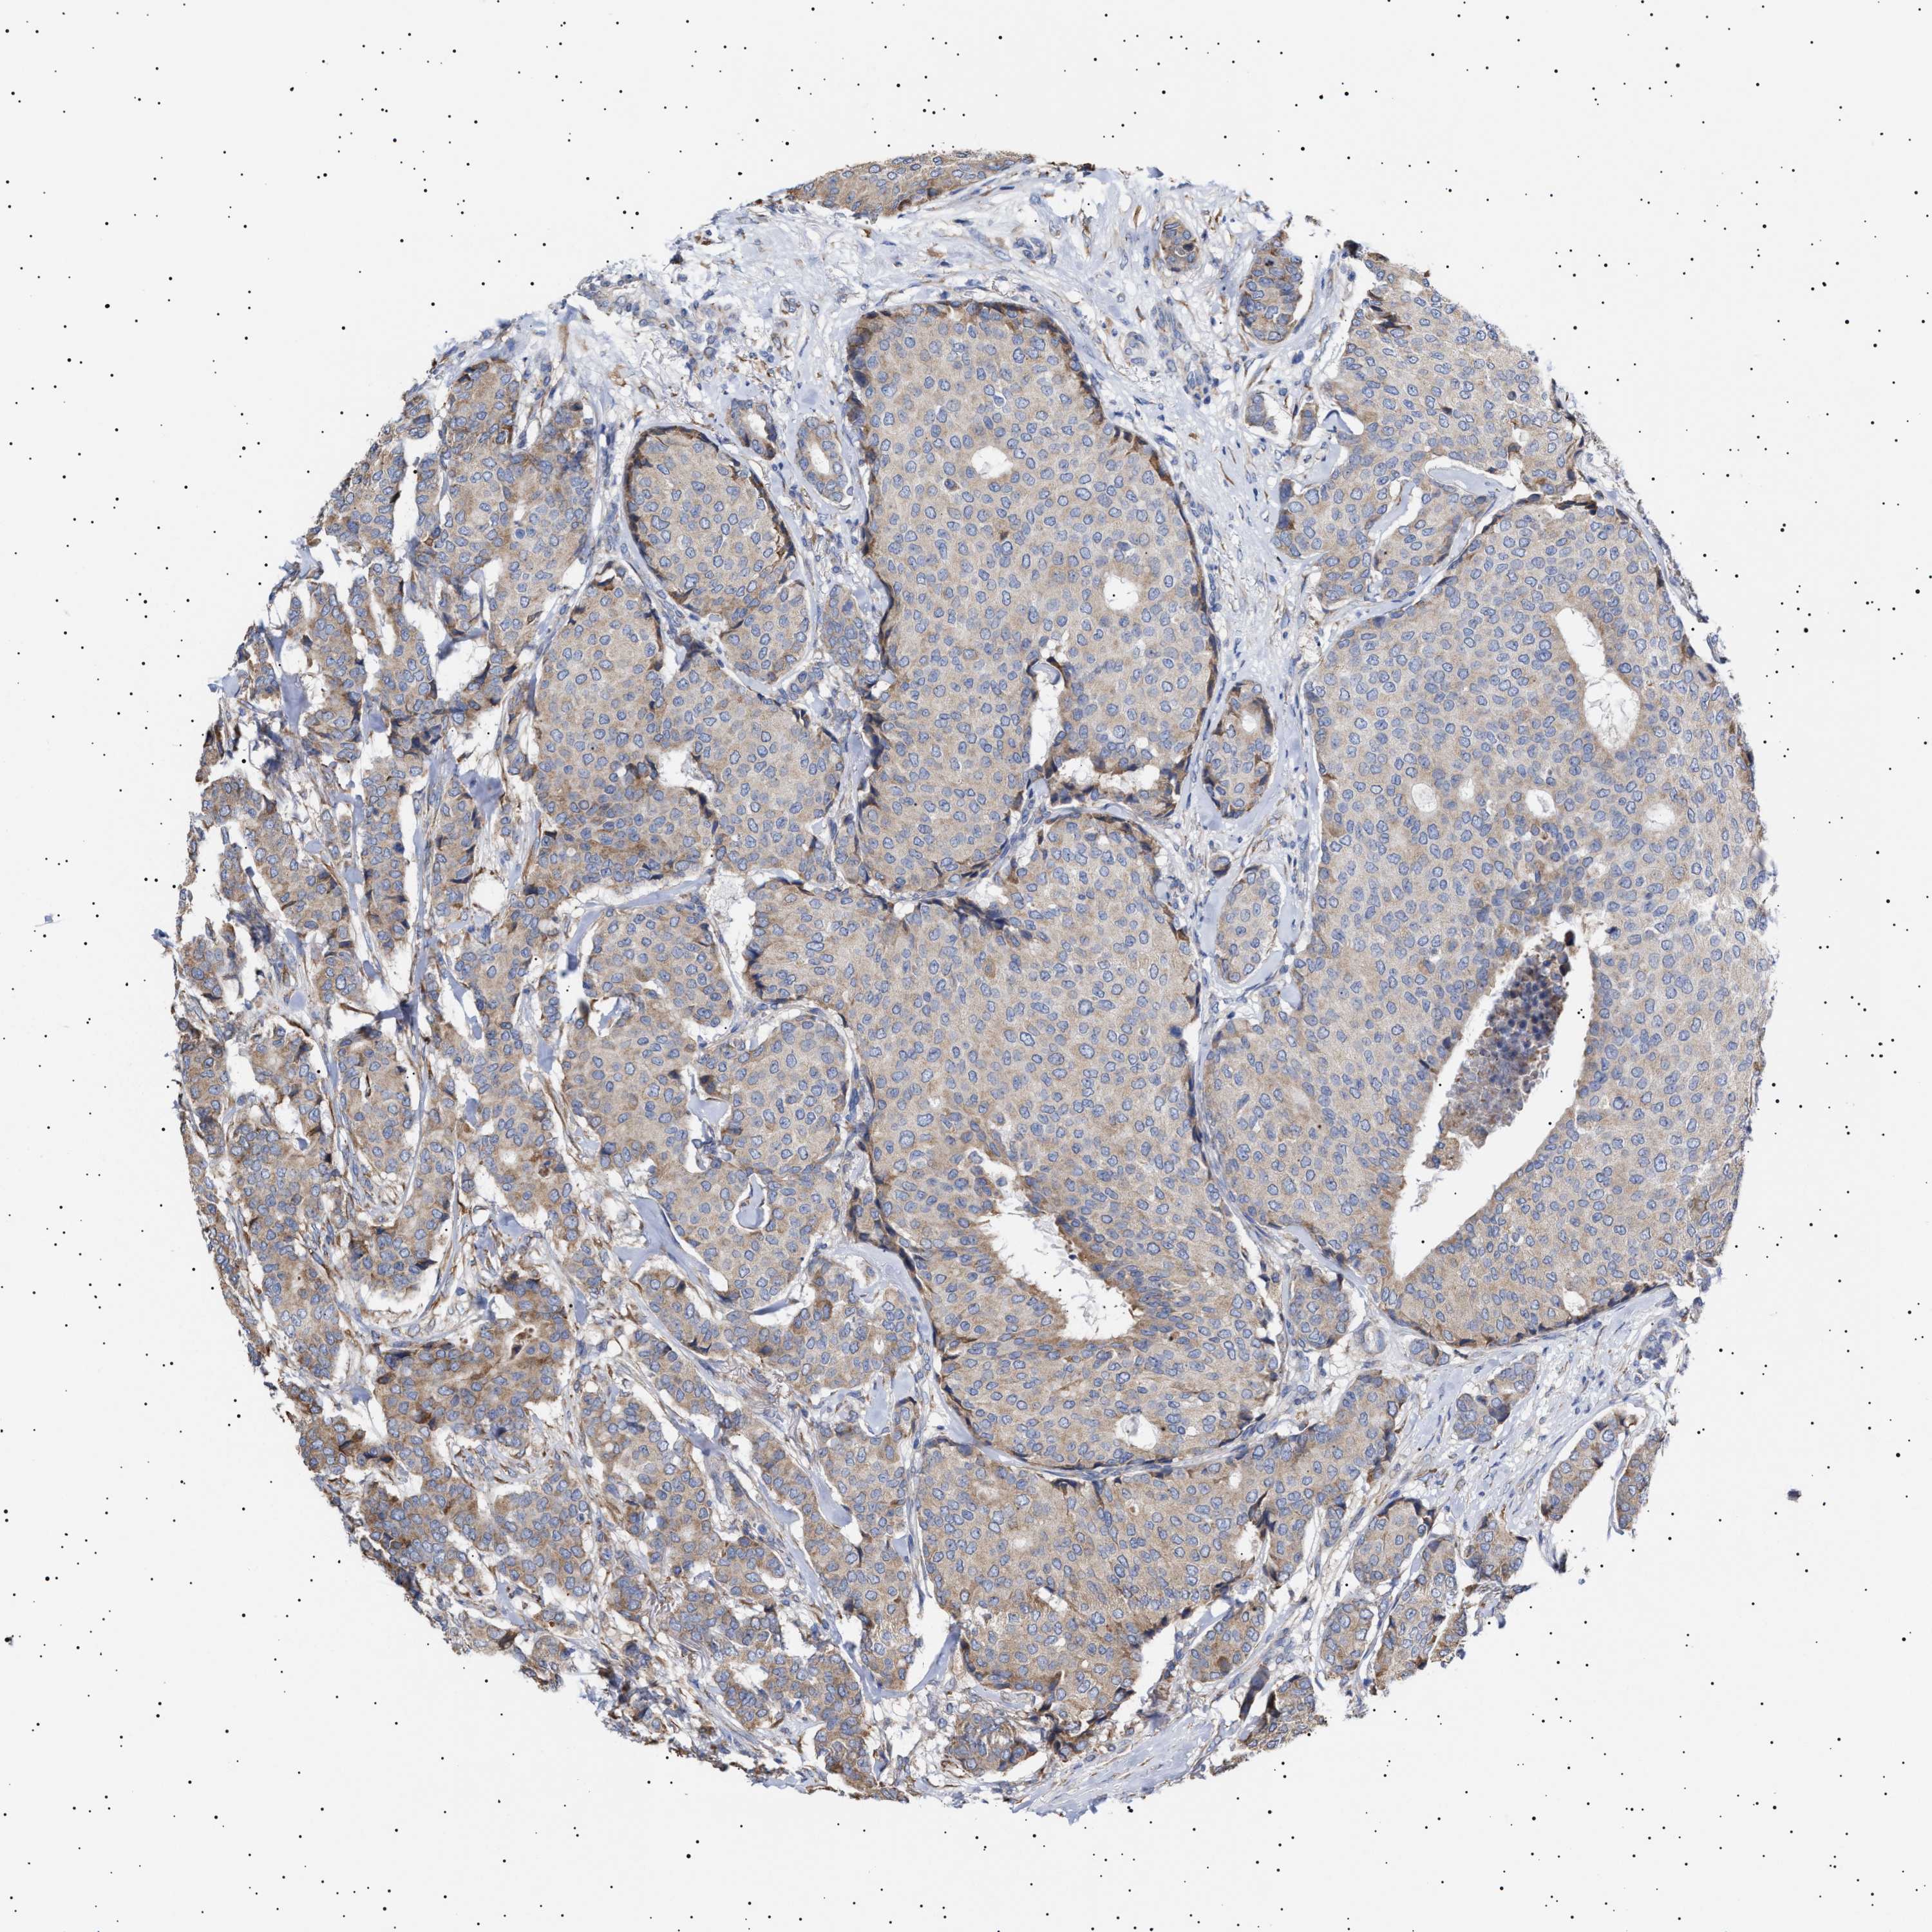

BRCA TCGA BRCA VALIDATION PROTEIN EXPRESSION

ANTIBODIES

AND

VALIDATION